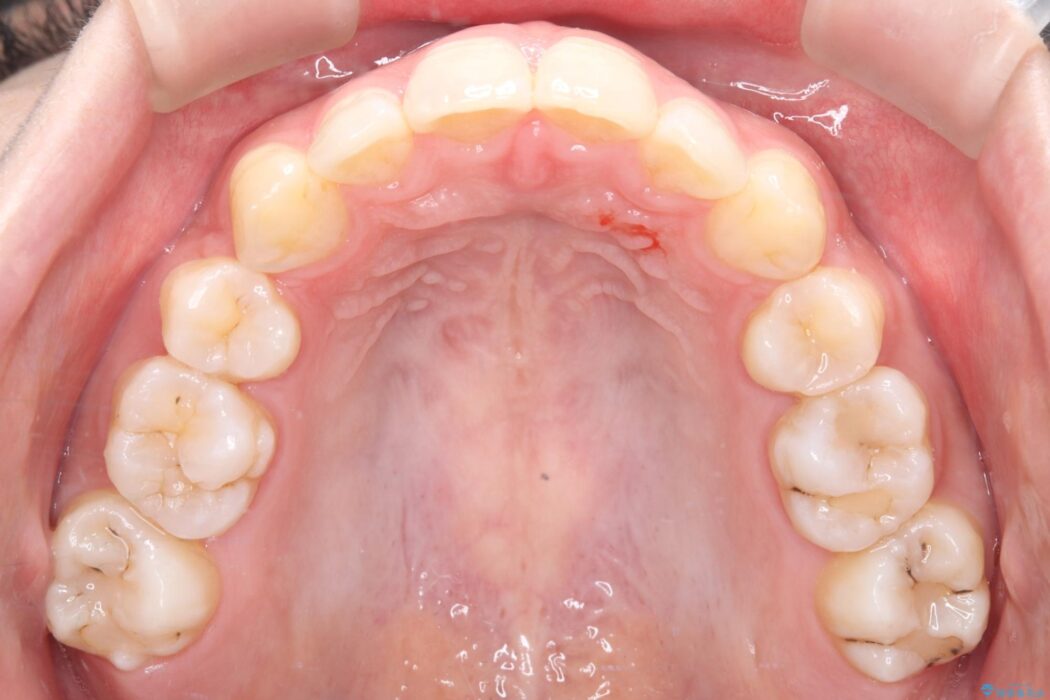

治療後について

長年の悩みだった重度の乱れが解消され、口元の突出感もすっきり改善。見た目も機能も安定した、理想的な歯並びを獲得していただけました。